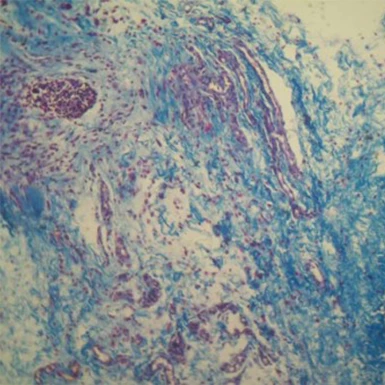

Рис. 6. Неоколлагеногенез и неоэластогенез в дерме кожи над имплантированной нитью из поли-L-молочной кислоты на 90-е сутки. Коллагеновые волокна окрашены в синий, эластиновые – в красный цвет7.

...

Рис. 7. Участок дермы над имплантированной нитью из полидиоксанона на 90-й день эксперимента. Увеличение доли эластиновых волокон (красный цвет) по отношению к коллагеновым (синий цвет) в дермальном слое7.